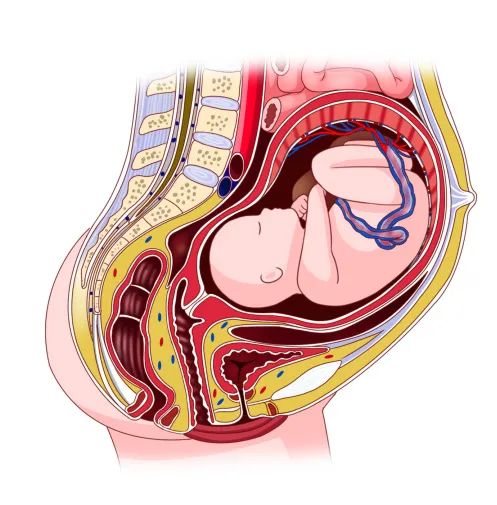

盆底功能障礙性疾病大部分來源于妊娠和分娩,懷孕時,隨著胎兒的慢慢長大,子宮的逐漸增大,胎位下移,盆底會變得松弛。分娩時,隨著胎兒的娩出,部分韌帶松裂,盆底肌彈性變差,無法將器官固定在正常位置。約有45%的女性在分娩后會發(fā)生不同程度的尿失禁、陰道松馳、子宮脫垂等盆底功能障礙性疾病。